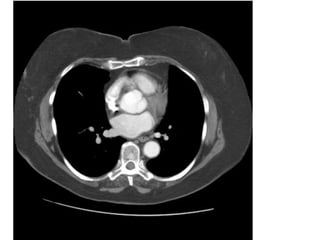

Figure 4. PE cấp ở BN nữ 32 tuổi, lâm sàng có đau ngực. CT cho thấy PE ở

nhánh phân thùy đáy – sau của động mạch thùy dưới (P). (mũi tên). Động mạch

bị tắc dãn lớn hơn các mạch máu kế cận.